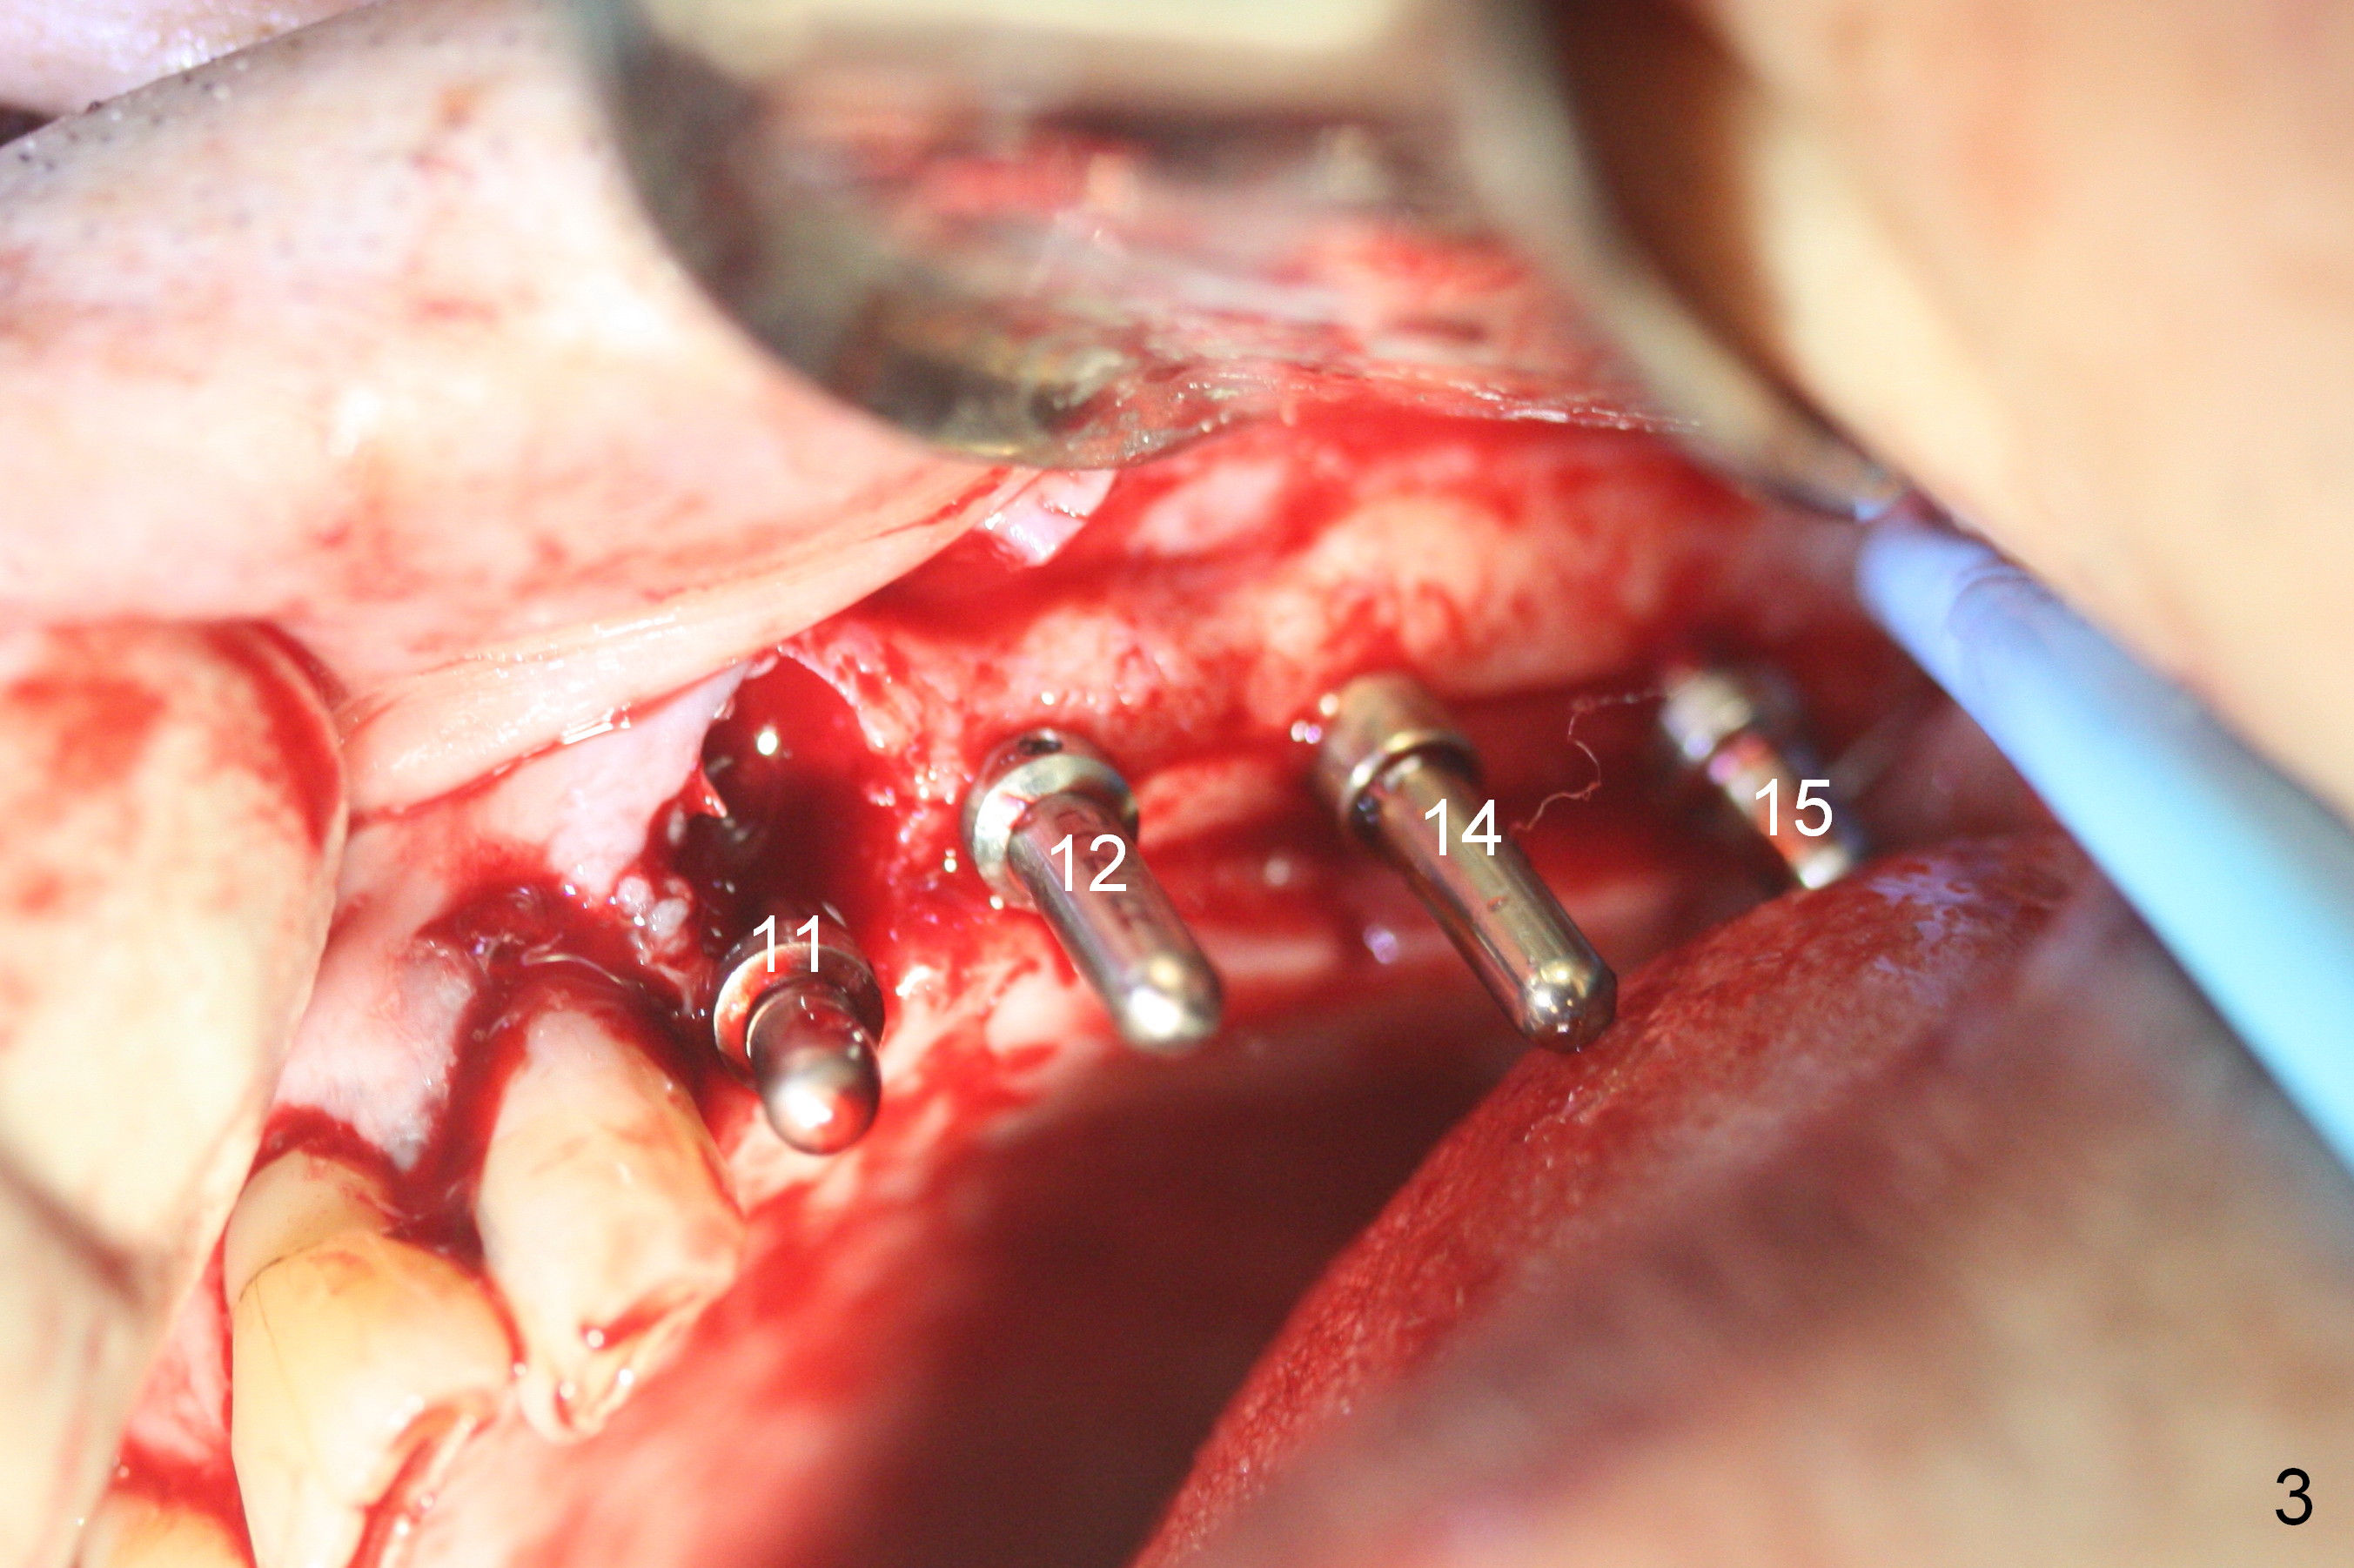

The edentulous ridge distal to #11 residual root is moderately atrophic (Fig.1). The ridge is split with 10 and 13 mm saws between initial osteotomies at #12,14 and 15 (Fig.2). Parallel pins are inserted for trajectory confirmation (Fig.3,4). The gap of the split ridge between #12 and 14 increases when bone expanders (2.7/3.6 mm) are being inserted. A 4.5x17 mm implant does not obtain primary stability at #12. When a 5x17 mm implant is being placed at #12, the buccal plate starts to crack. When the same implant is placed at #14, the crack appears to get larger. Drills are used to finish osteotomy at #14 with force being applied palatally. When the implant is re-inserted, the buccal plate fractures does not appears to get worse (Fig.5 <). In contrast, there is no obvious increase in the gap between #14 and 15 when bone expanders are being used at #15. To avoid complication, drills are used to finish osteotomy before placing a 4.5x14 mm at #15 (Fig.7 (#11: 4.5x17 mm)). CBCT shows that the bone density at #12 and 14 (400-500 Hounsfield units (HU)) is higher than that at #15 (200-300 HU). Ridge split is successful when HU is <200 with smaller diameter implants.